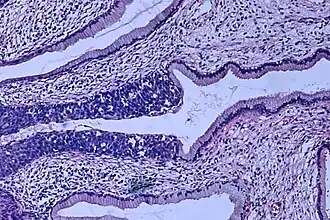

Description de cette image, également commentée ci-après

De gauche vers le centre de l'image, carcinome in situ (violet foncé) atteignant les glandes cervicales[1].